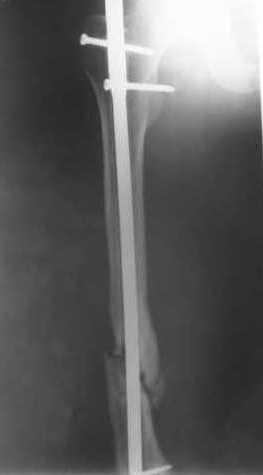

Пациенту М., 30-ти лет, 1,5 года назад в одной из московских больниц был выполнен остеосинтез бедренной кости штифтом UFN (диаметр штифта 9 мм).

К нам больной поступил с признаками ложного сустава бедренной кости, перелома

штифта и дистального блокирующего винта (images 1,2,3).

27 марта выполнено удаление блокирующих винтов (сломанный винт пришлось высверливать цапфен-бором), сломанного штифта (дистальный фрагмент удален через канал, образованный разверткой из коленного сустава - image 4),

рассверливание костно-мозгового канала, реостеосинтез штифтом UFN (при проведении штифта в дистальном отломке мы использовали поляризующий винт, диаметр штифта 10 мм). После операции в связи гемартрозом дважды (на 1 и 3 сутки) выполняли пункцию коленного сустава. Сейчас признаков скопления жидкости в полости сустава нет. Послеоперационные рентгенограммы - images 5, 6, 7.